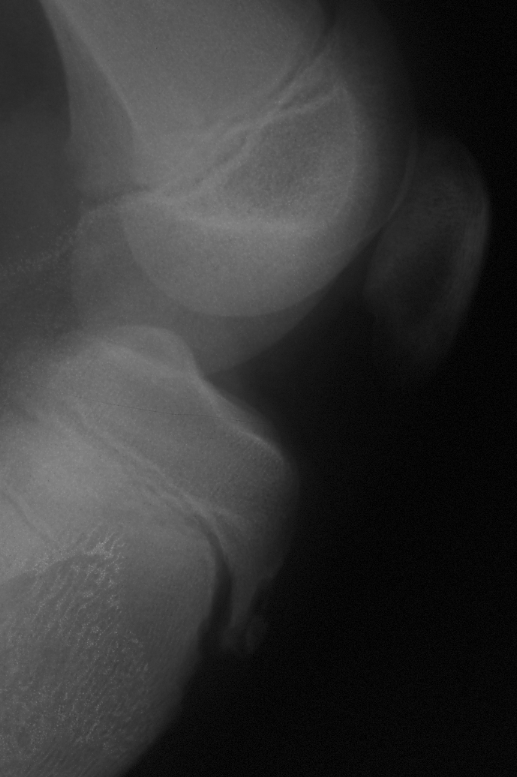

Source: boullakxs.pages.dev Morbus OsgoodSchlatter Heilpraxis , Gestern hatte ich dann einen Termin bei einem Orthopäden und nachdem er sich mein Röntgenbild angeschaut hat meinte er, ich hätte das sogenannte Morbus Osgood Schlatter in der Pubertät gehabt und daraus würde jetzt der Reizzustand Tuberositas tibiae resultieren. Hallo, Ich bin 18 und leide seit 4 Jahren an Morbus Schlatter